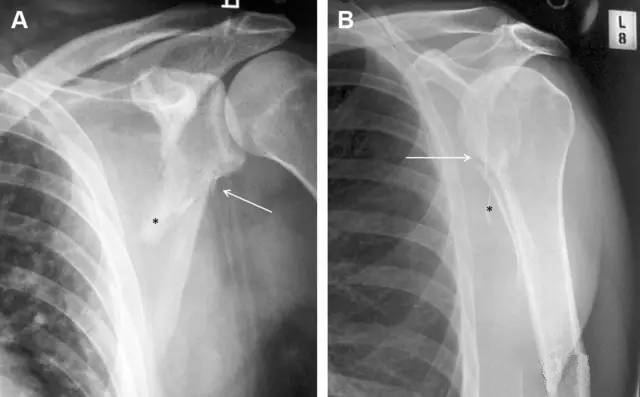

图 肩胛骨骨折正侧位片:由于骨块的叠加,(A)前后位片示「V」形高密度影(*),肩胛颈下方可见骨皮质碎片(箭头);(B)侧位片示骨皮质中断,骨折段移位,但由于肱骨的重叠遮挡,决断往往比较困难